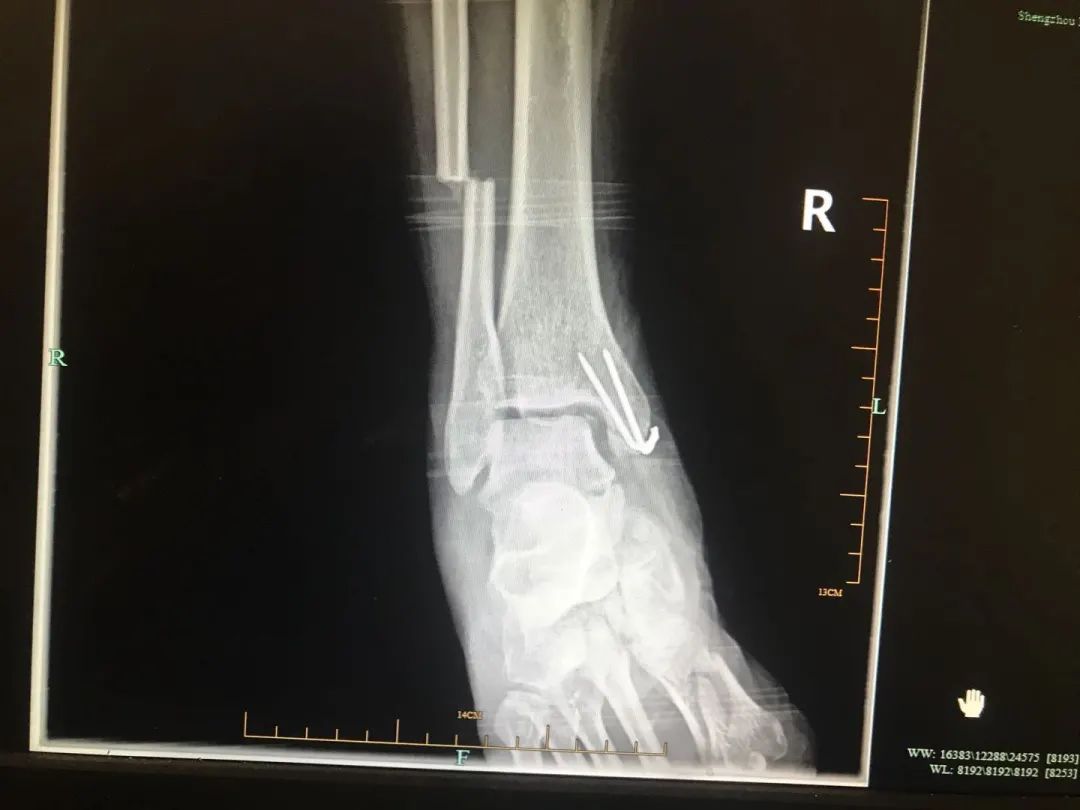

首先就是要将其右腿近十处骨折进行紧急救治。右股骨中段粉碎性骨折、右股骨颈骨折、右胫骨平台骨折、右腓骨小头骨折、右腓骨下段骨折、右髌骨骨折、开放性右踝关节骨折、右第一趾不全离断、右4、5趾缺损、右踝软组织挫裂伤……

两位骨科医师王刚祥与张伟江早已身经百战,面对受伤如此严重的右下肢还是倒吸了一口冷气。生命永远是第一位,王刚祥与张伟江立即争分夺秒为其实施紧急手术,清除伤面内坏死及污染组织、残端修整、复位、固定、缝合一项项操作有条不紊的进行,手术顺利完成。但由于邹先生伤情较重,生命体征极不平稳,且失血多,血压低,术后转入ICU继续治疗。